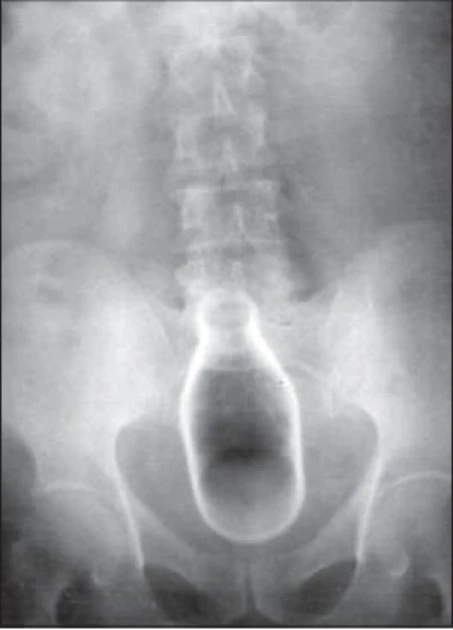

Обычно делают несколько рентгеновских снимков, чтобы точно определить место нахождения инородного тела. Инородные тела из малоконтрастного материала (например, пластика) могут потребовать ультразвукового исследования или компьютерной томографии[23]. Магнитно-резонансная томография противопоказана, особенно если неизвестен материал инородного тела. Инородные тела прямой кишки могут проникать глубоко в толстую кишку, при определённых обстоятельствах вплоть до правого изгиба ободочной кишки[9].